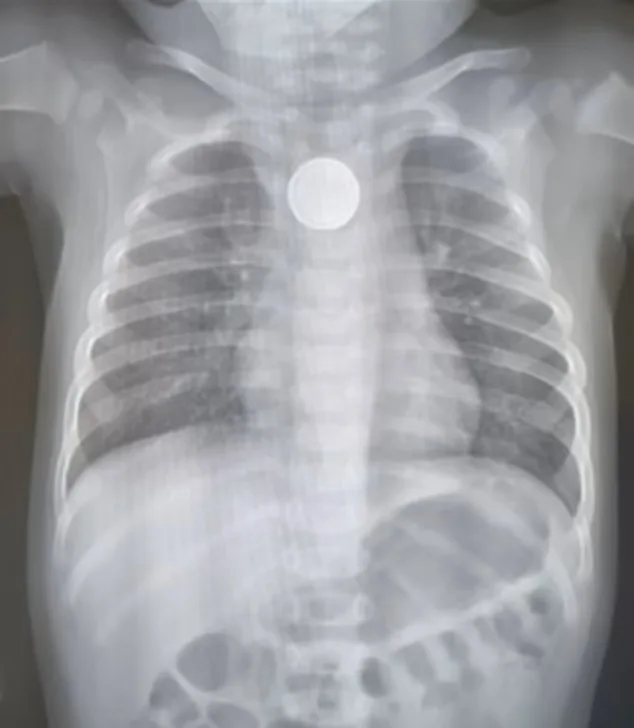

Back at the same hospital, a scan showed that Amity had swallowed a button battery and it was lodged in her oesophagus.

By the time I arrived with Dad that night, the battery, the size of a 10-cent coin, had been successfully removed.

Tragically, the battery acid had burnt a hole in our girl’s oesophagus.